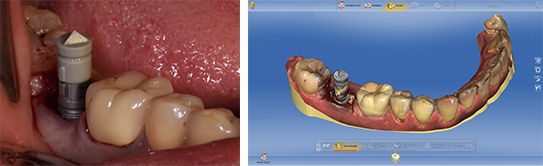

Dans certaines situations cliniques, il peut être intéressant de réaliser un pilier de cicatrisation anatomique ou une restauration provisoire de façon extemporanée. L’empreinte optique est alors réalisée juste après la mise en place de l’implant (Fig. 9 a et b).

5. Empreinte optique de l’implant :